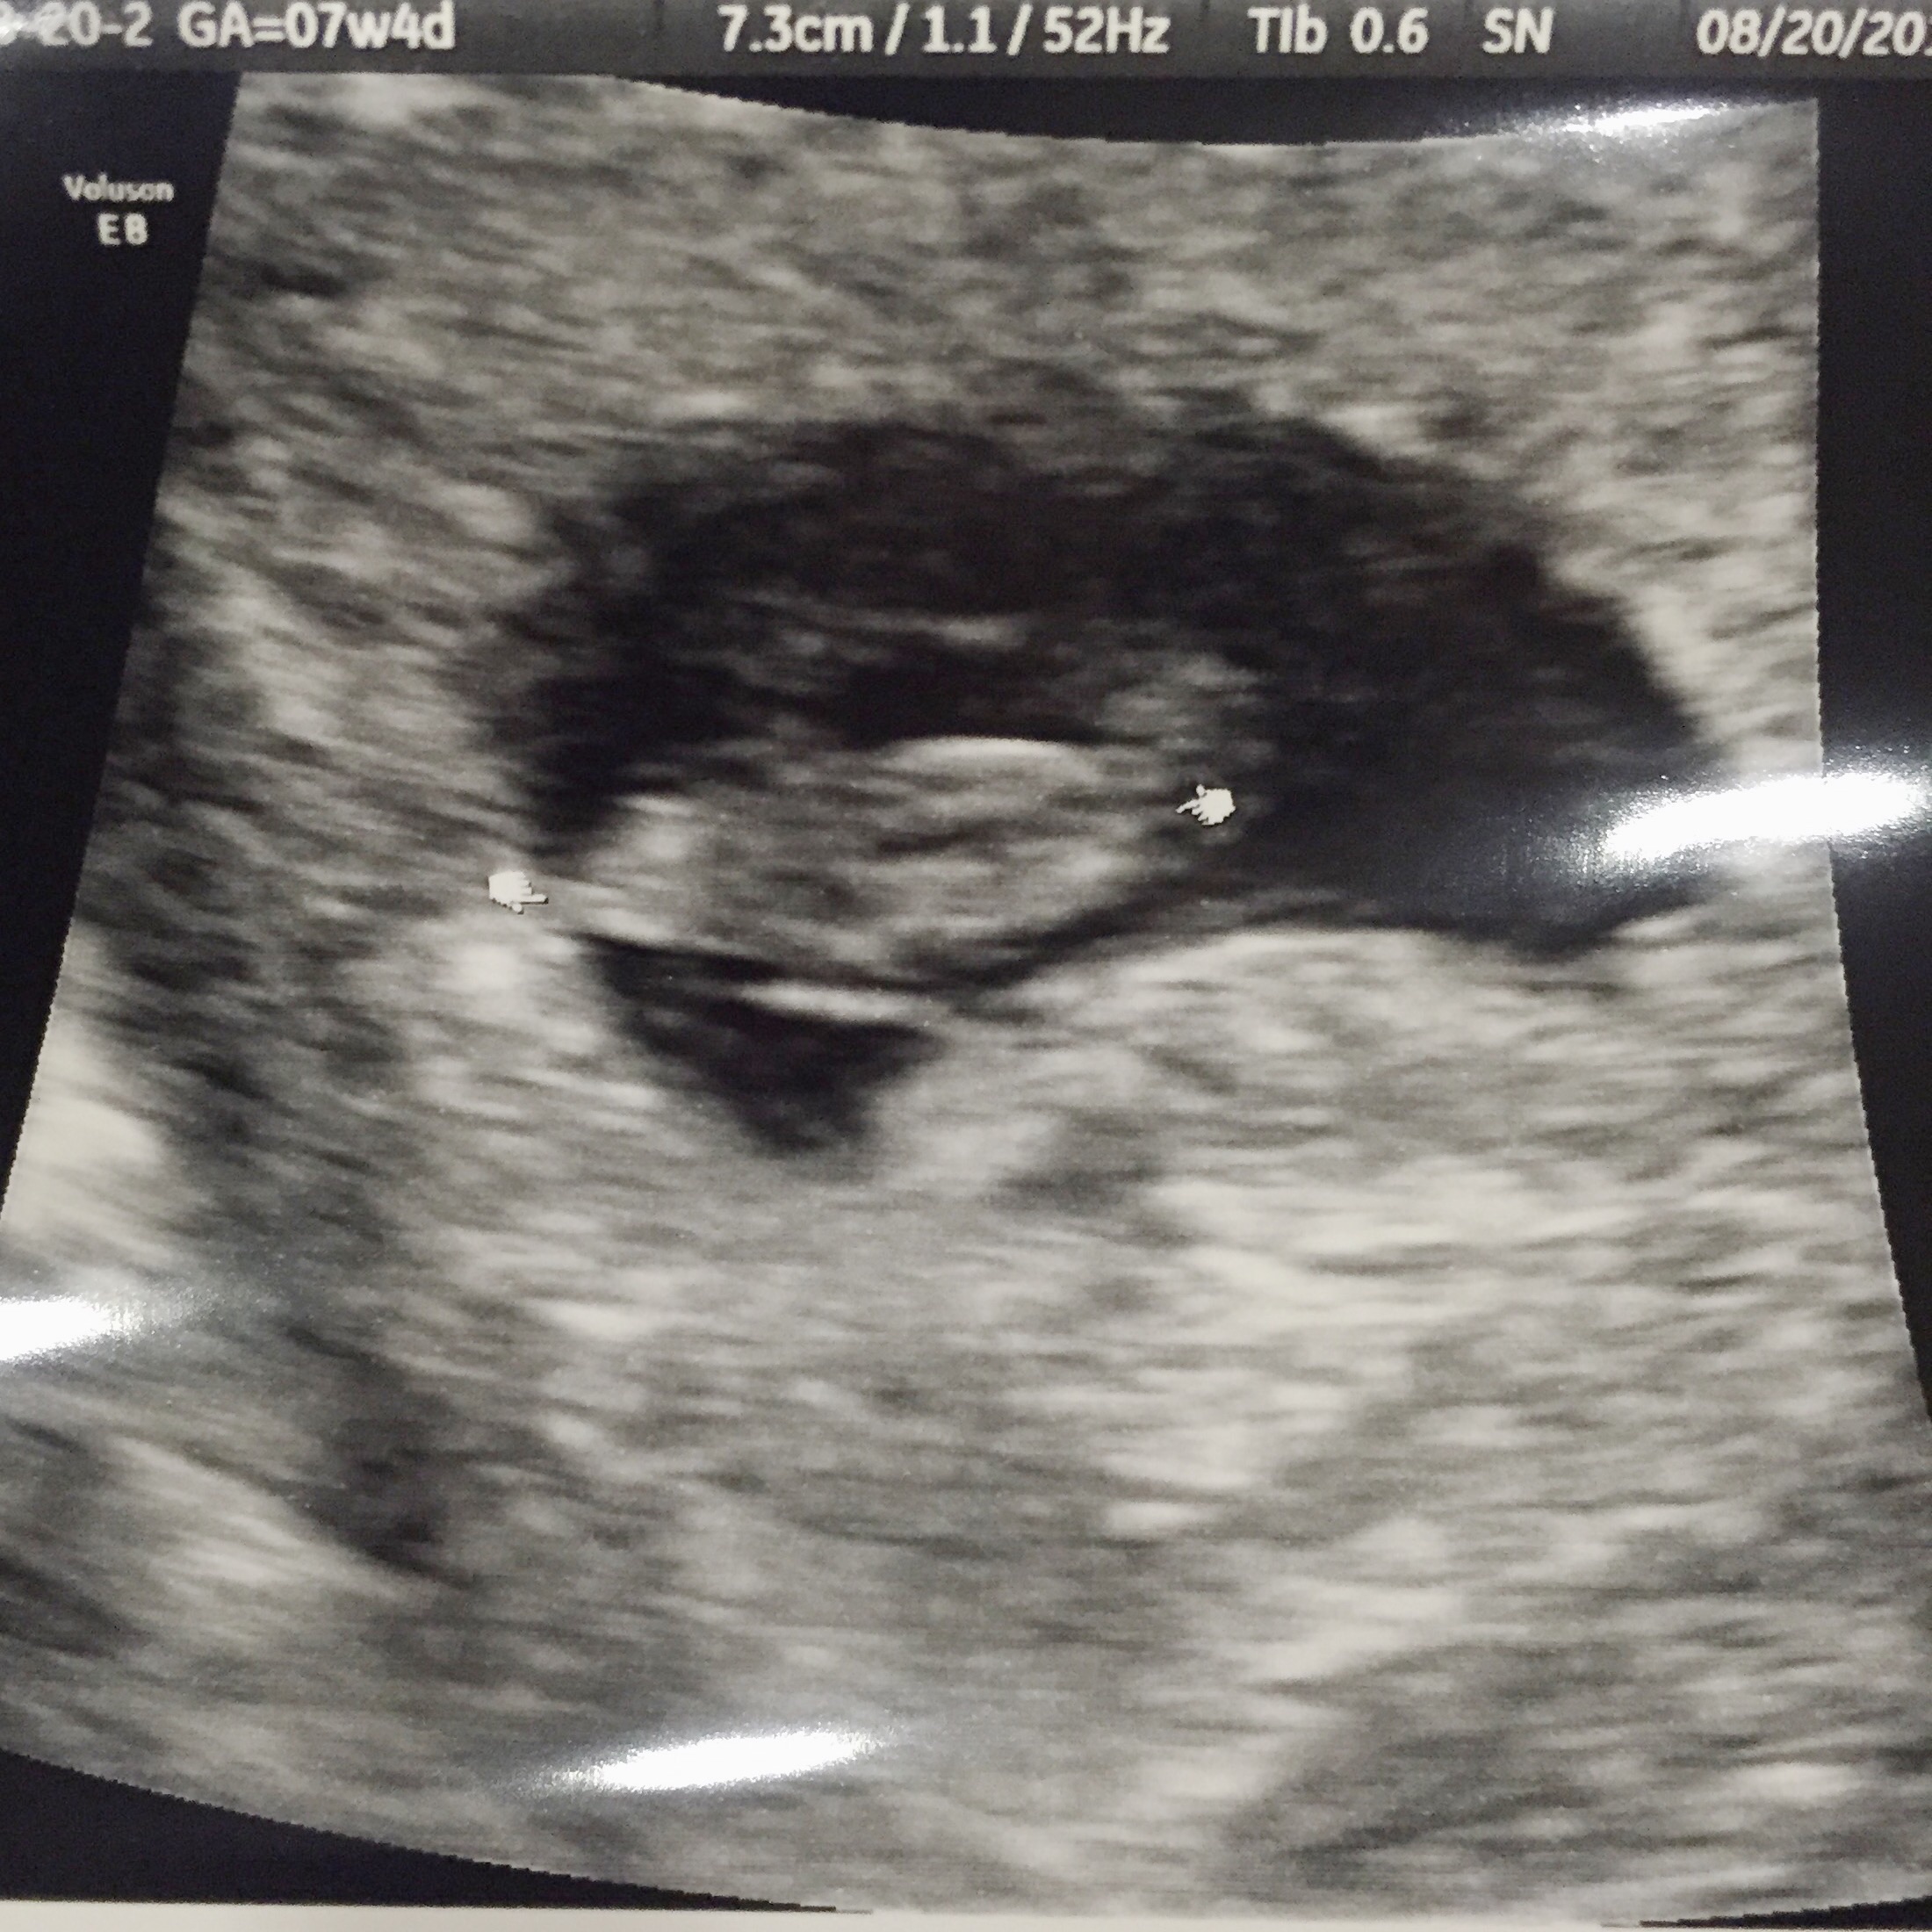

I am expecting twins. At 6w6day pregnant I had my u/s on 8/13 ( baby a measure at seven weeks and baby b 6w5days. Both of them doing great with strong hearts beats. So happy and exciting for all of us.